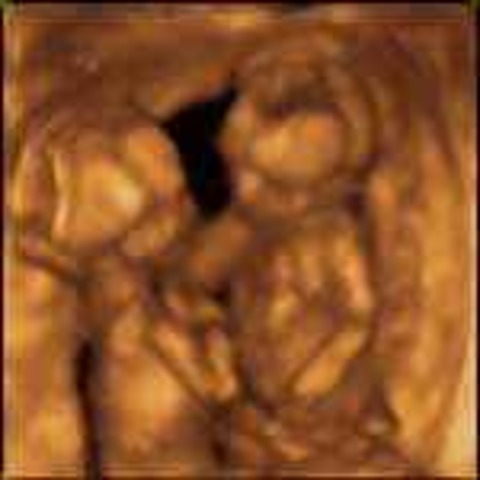

• Week Twenty: The Halfway Point

Week Twenty: The Halfway Point

The mother's voice is recognizable. The mom can start feeling the fetus move. The hair also starts to grow.